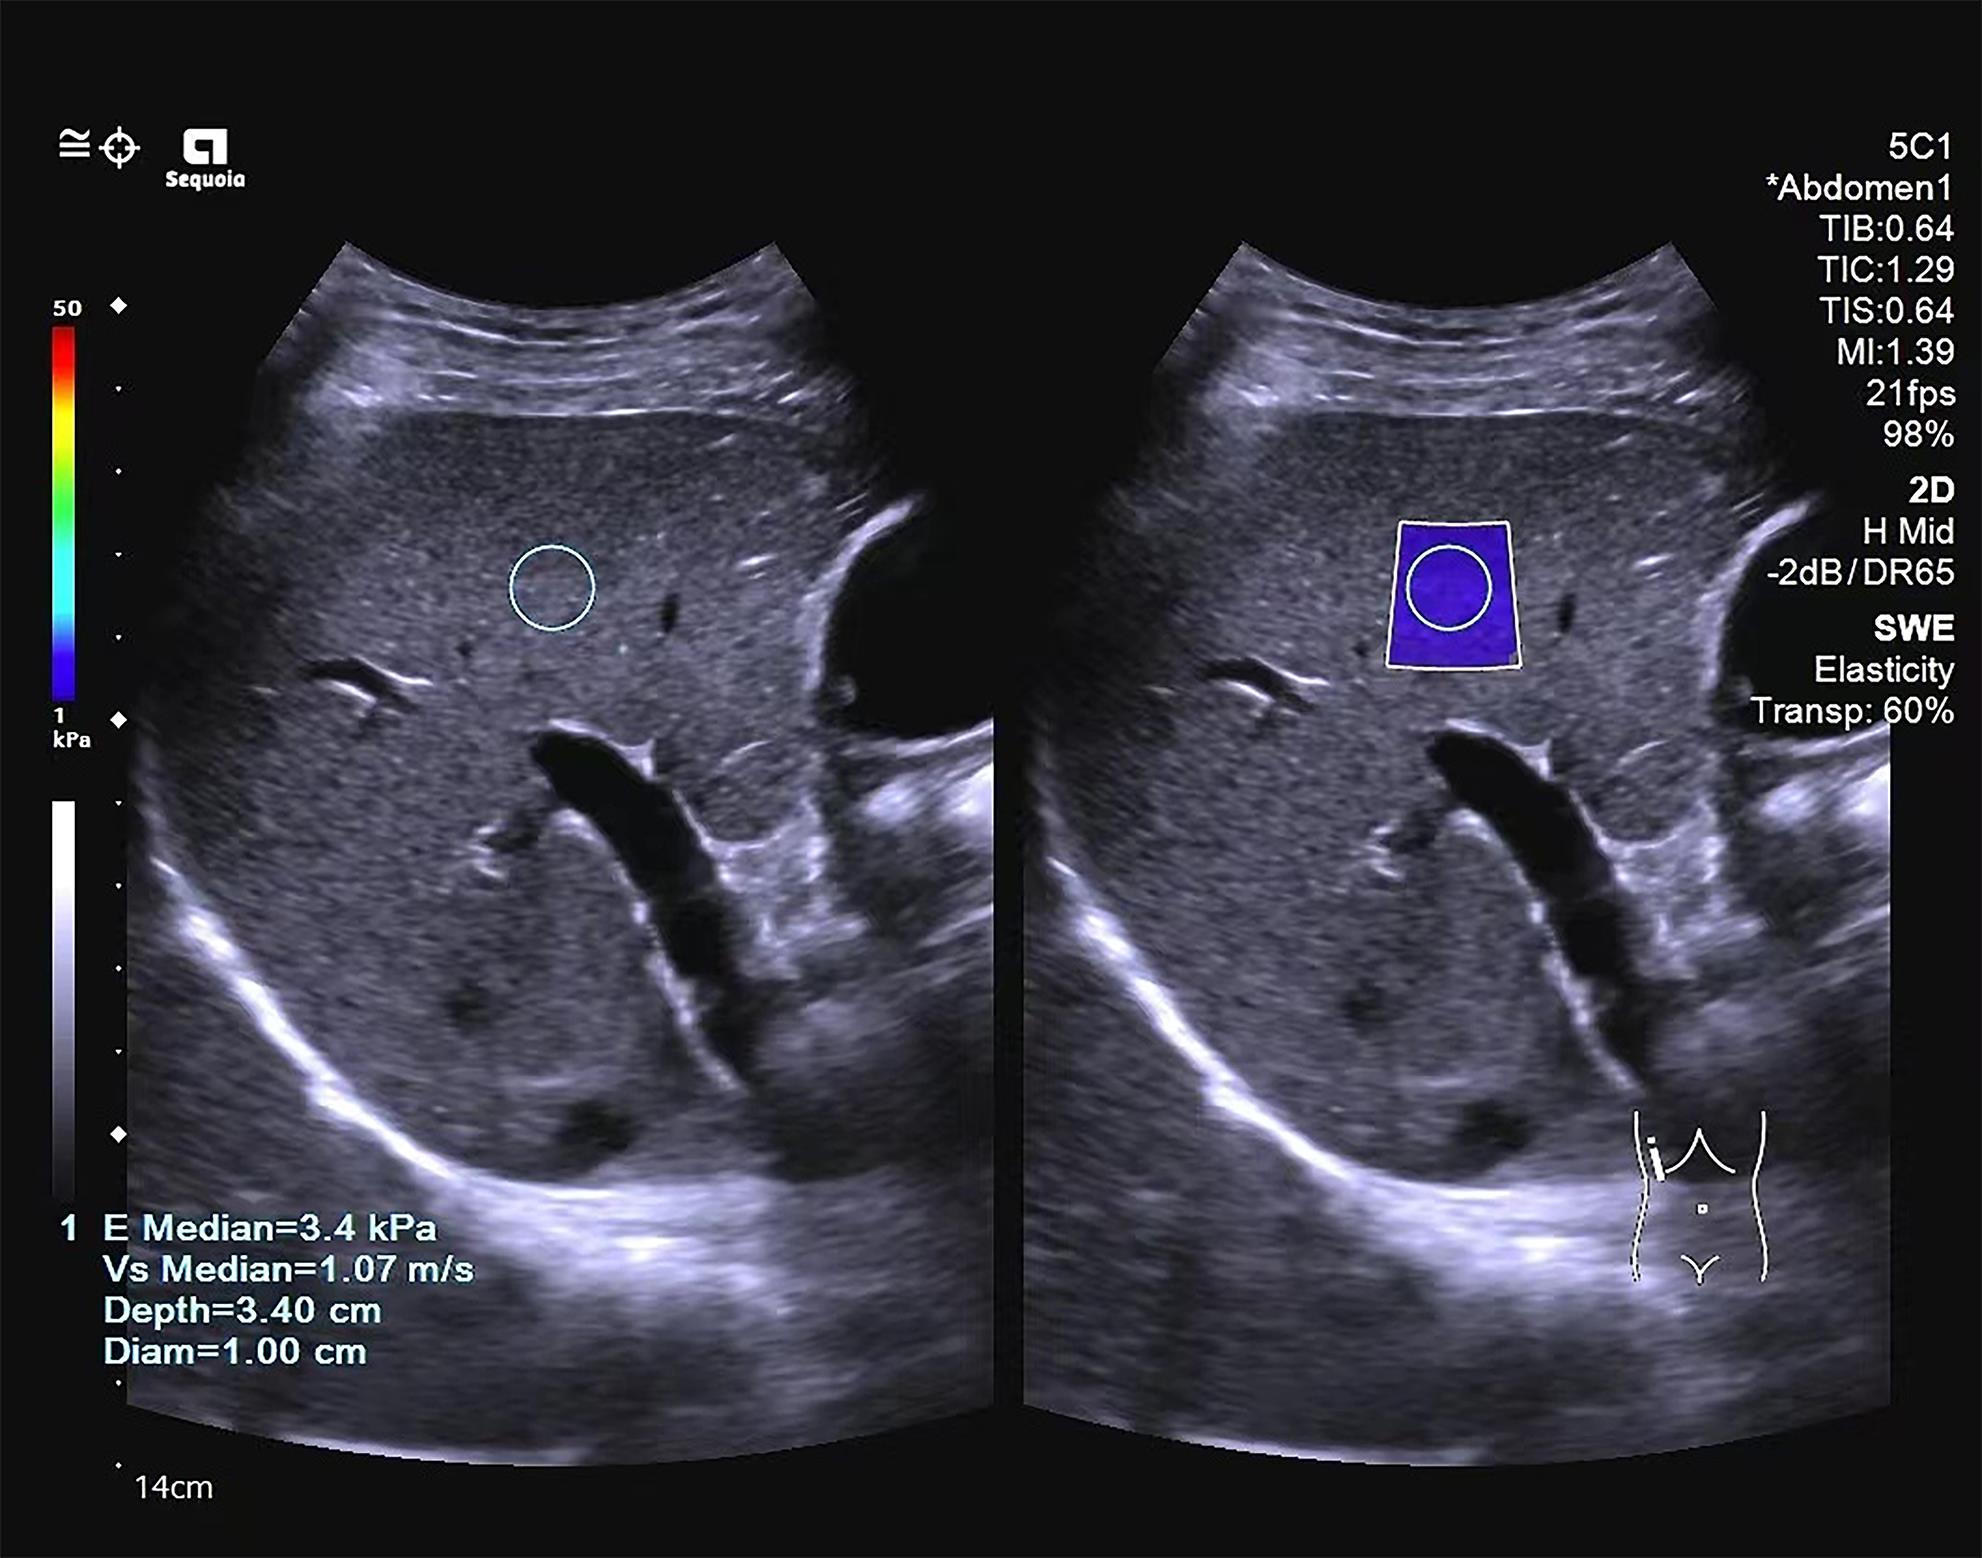

Application value of two-dimensional shear wave elastography and serological models in the staging of liver fibrosis in patients with chronic hepatitis B

Yujie HUANG, Siyi FENG

2024, 40(3): 509-515. DOI: 10.12449/JCH240312

Abstract(1117) HTML (280) PDF (1188KB)(84)

Abstract:

Objective  To investigate the value of two-dimensional shear wave elastography (2D-SWE) or serological models used alone or in combination in determining the stage of liver fibrosis in patients with chronic hepatitis B.  Methods  A retrospective analysis was performed for the clinical data of 327 patients with chronic hepatitis B who were admitted to Mengchao Hepatobiliary Hospital of Fujian Medical University from August 2020 to August 2022 and underwent 2D-SWE and liver histopathological examination, including sex, age, serological markers, and 2D-SWE results. According to the degree of liver fibrosis, they were divided into S0-S1, S≥2, S≥3, and S=4 groups, and the serological models were calculated based on serological markers. A Spearman correlation analysis was used to investigate the correlation of 2D-SWE and serological models with liver fibrosis stage; the receiver operating characteristic curve was plotted with the results of liver histopathology as the standard to compare the efficiency of each parameter used alone or in combination in determining the stage of liver fibrosis; the Delong test was used to investigate the difference between different methods.  Results  Liver stiffness measurement measured by 2D-SWE was strongly correlated with the stage of liver fibrosis (r=0.741, P<0.001), and as for the serological model, six markers (APRI, FIB-4, GPR, GP, RPR, and S index), other than AAR, were positively correlated with the stage of liver fibrosis (all P<0.001). 2D-SWE had an area under the ROC curve (AUC) of 0.878, 0.932, and 0.942, respectively, in the diagnosis of S≥2, S≥3, and S=4 liver fibrosis (all P<0.001), with an optimal cut-off value of 6.9 kPa, 7.9 kPa, and 9.4 kPa, respectively. Among the serological models, APRI had the largest AUC of 0.788 and 0.875, respectively, in the diagnosis of S≥2 and S=4 liver fibrosis, and S index had the largest AUC of 0.846 in the diagnosis of S≥3 liver fibrosis. In the diagnosis of S≥2, S≥3, and S=4 liver fibrosis, 2D-SWE combined with APRI increased the AUC values to 0.887, 0.938, and 0.950, respectively, and 2D-SWE combined with S index increased the AUC values to 0.879, 0.935, and 0.941, respectively, while there were no significant differences between 2D-SWE and the above combinations (P>0.05).  Conclusion  2D-SWE has a better diagnostic efficacy than the above seven serological models in determining liver fibrosis stage. The serological models have a certain diagnostic value, among which APRI and S index have a relatively high diagnostic value. There is no significant difference between 2D-SWE and 2D-SWE combined with serological models, and such combinations cannot significantly improve diagnostic efficiency. Therefore, further studies are needed to explore new combinations of diagnostic methods.